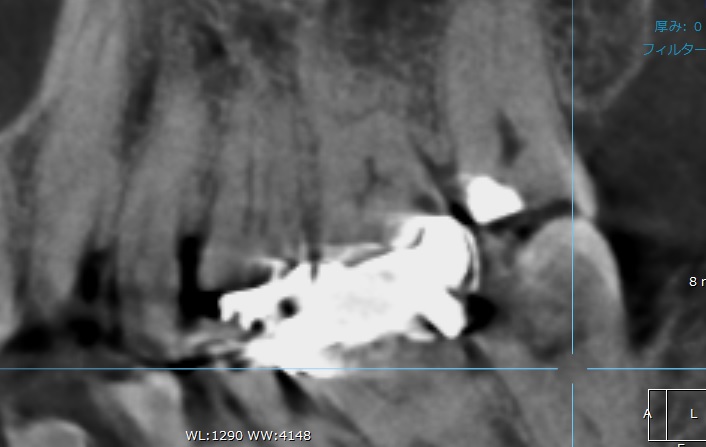

こちらの歯のCT写真をお見せします。

先ほどの青い矢印の所に黒い丸い影が出てきました!

「なんだ、CTで分かるじゃん!」

そうです。CTで分かる場合もありますが、しかし、

黒い影は手前の歯にもありませんか?

少し見る断面を変えてみましょう。

手前の歯に大きな黒い影が出てきました。さらに他の歯にも!

これは虫歯でしょうか?

いいえ、他の歯は虫歯になっていません。

CTの検査では、周りの歯に金属が入っていると、金属が画像で反射してしまい、

白い光が強調されたり、周囲に黒い影が出てきます。

ですので、黒い影が虫歯なのか、金属の反射の影響によるものなのか判別がつきません。

CT検査だけで虫歯の診断をすることはできませんし、レントゲン検査より優れた精密検査ができるわけではないのです。